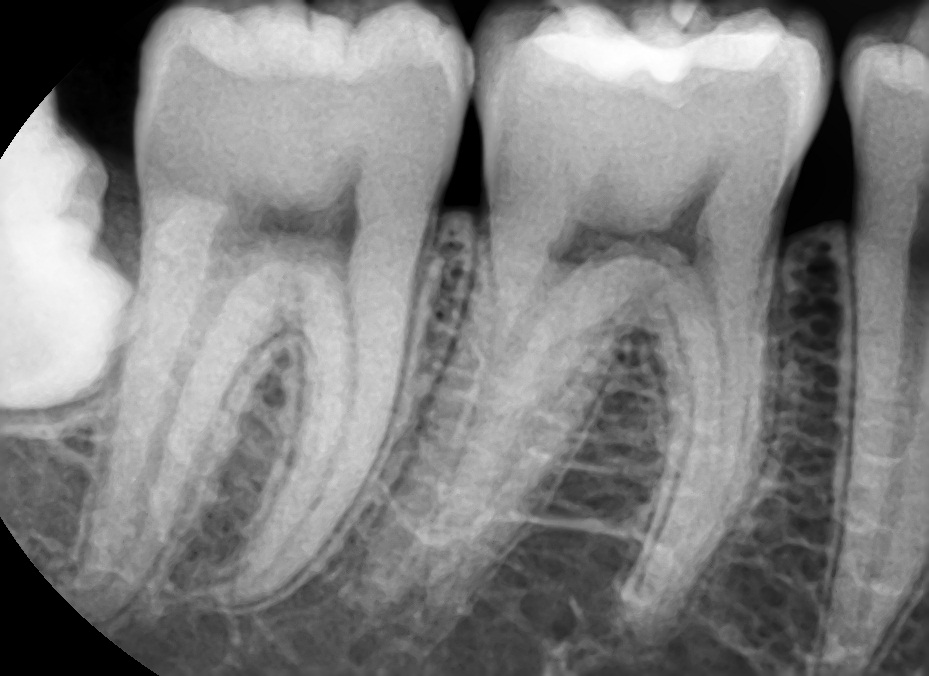

상기된 사진과 같은 치아상태에서 의사선생님이 국소적 법랑질우식이있으나 지켜보자했습니다. 헌데 요즘 게을러져서 한달 반정도를 4일에한번주기로 꼼꼼하게양치하고 치실질하는 식으로 했었는데요, 이것이 충치를 한달 반동안에 신경치료해야할만큼 위험하게 번질수도있나요?

21세 남성이고 3년간 안닦았다가 법랑질에 우식생긴이력이 있는지라 좀 우려스럽습니다

사진에서 보기에는 범랑질 표면에 살짝 표면충치가 생긴 것으로 보입니다. 범랑질 표면에 생긴 충치가 한달반 만에 상아질로 까지 진행될 가능성은 희박합니다.

충치가 교합면에도 잇고 치아 사이에도 충치가 잇는거 같습니다. 치료를 받으셔야될것같습니다.